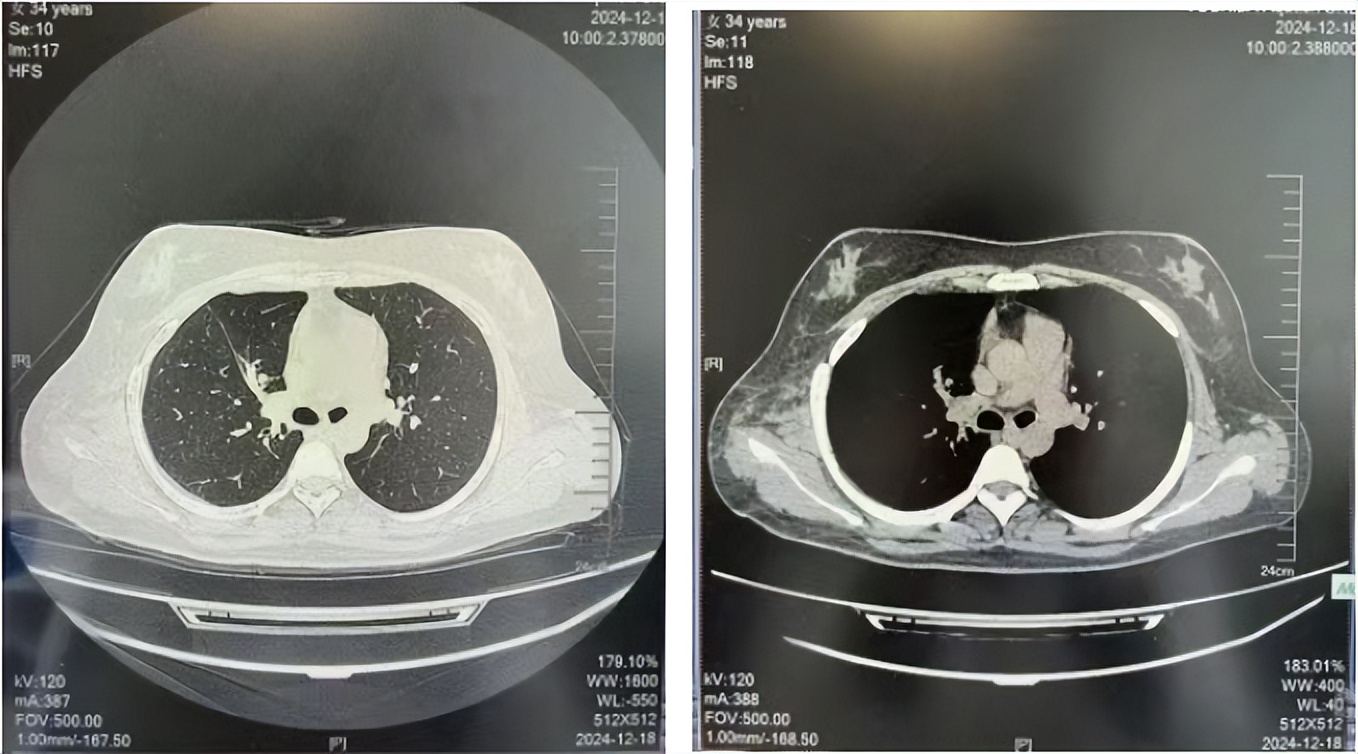

2016年1月复查CT提示支气管截断可见新发小结节,一线治疗采用培美曲塞+DDP方案化疗4周期(培美曲塞3.36,DDP 480mg)。化疗后复查胸部CT:右肺见不规则结节样影,最大层面大小约19mm*8mm,较前比较明显增大,疗效评估PD。2017.3-2017.4予单药多西他赛化疗3周期,疗效评估SD。2018年5月末复查CT提示结节较前增大,评效为PD,2018年6-10月予多西他赛+CBP化疗4周期,疗效评估SD。2022年5月患者出现活动后气短,复查胸部CT示右肺膨胀不良;右侧胸腔积液增多。胸腔积液包埋病理示符合肺腺癌细胞。行NGS基因检测:EML4:exon13-ALK:exon20融合。PD-L1(克隆号22C3)TPS<1%。

2018.07

2022.05

2022.08

2023.05

2024.12